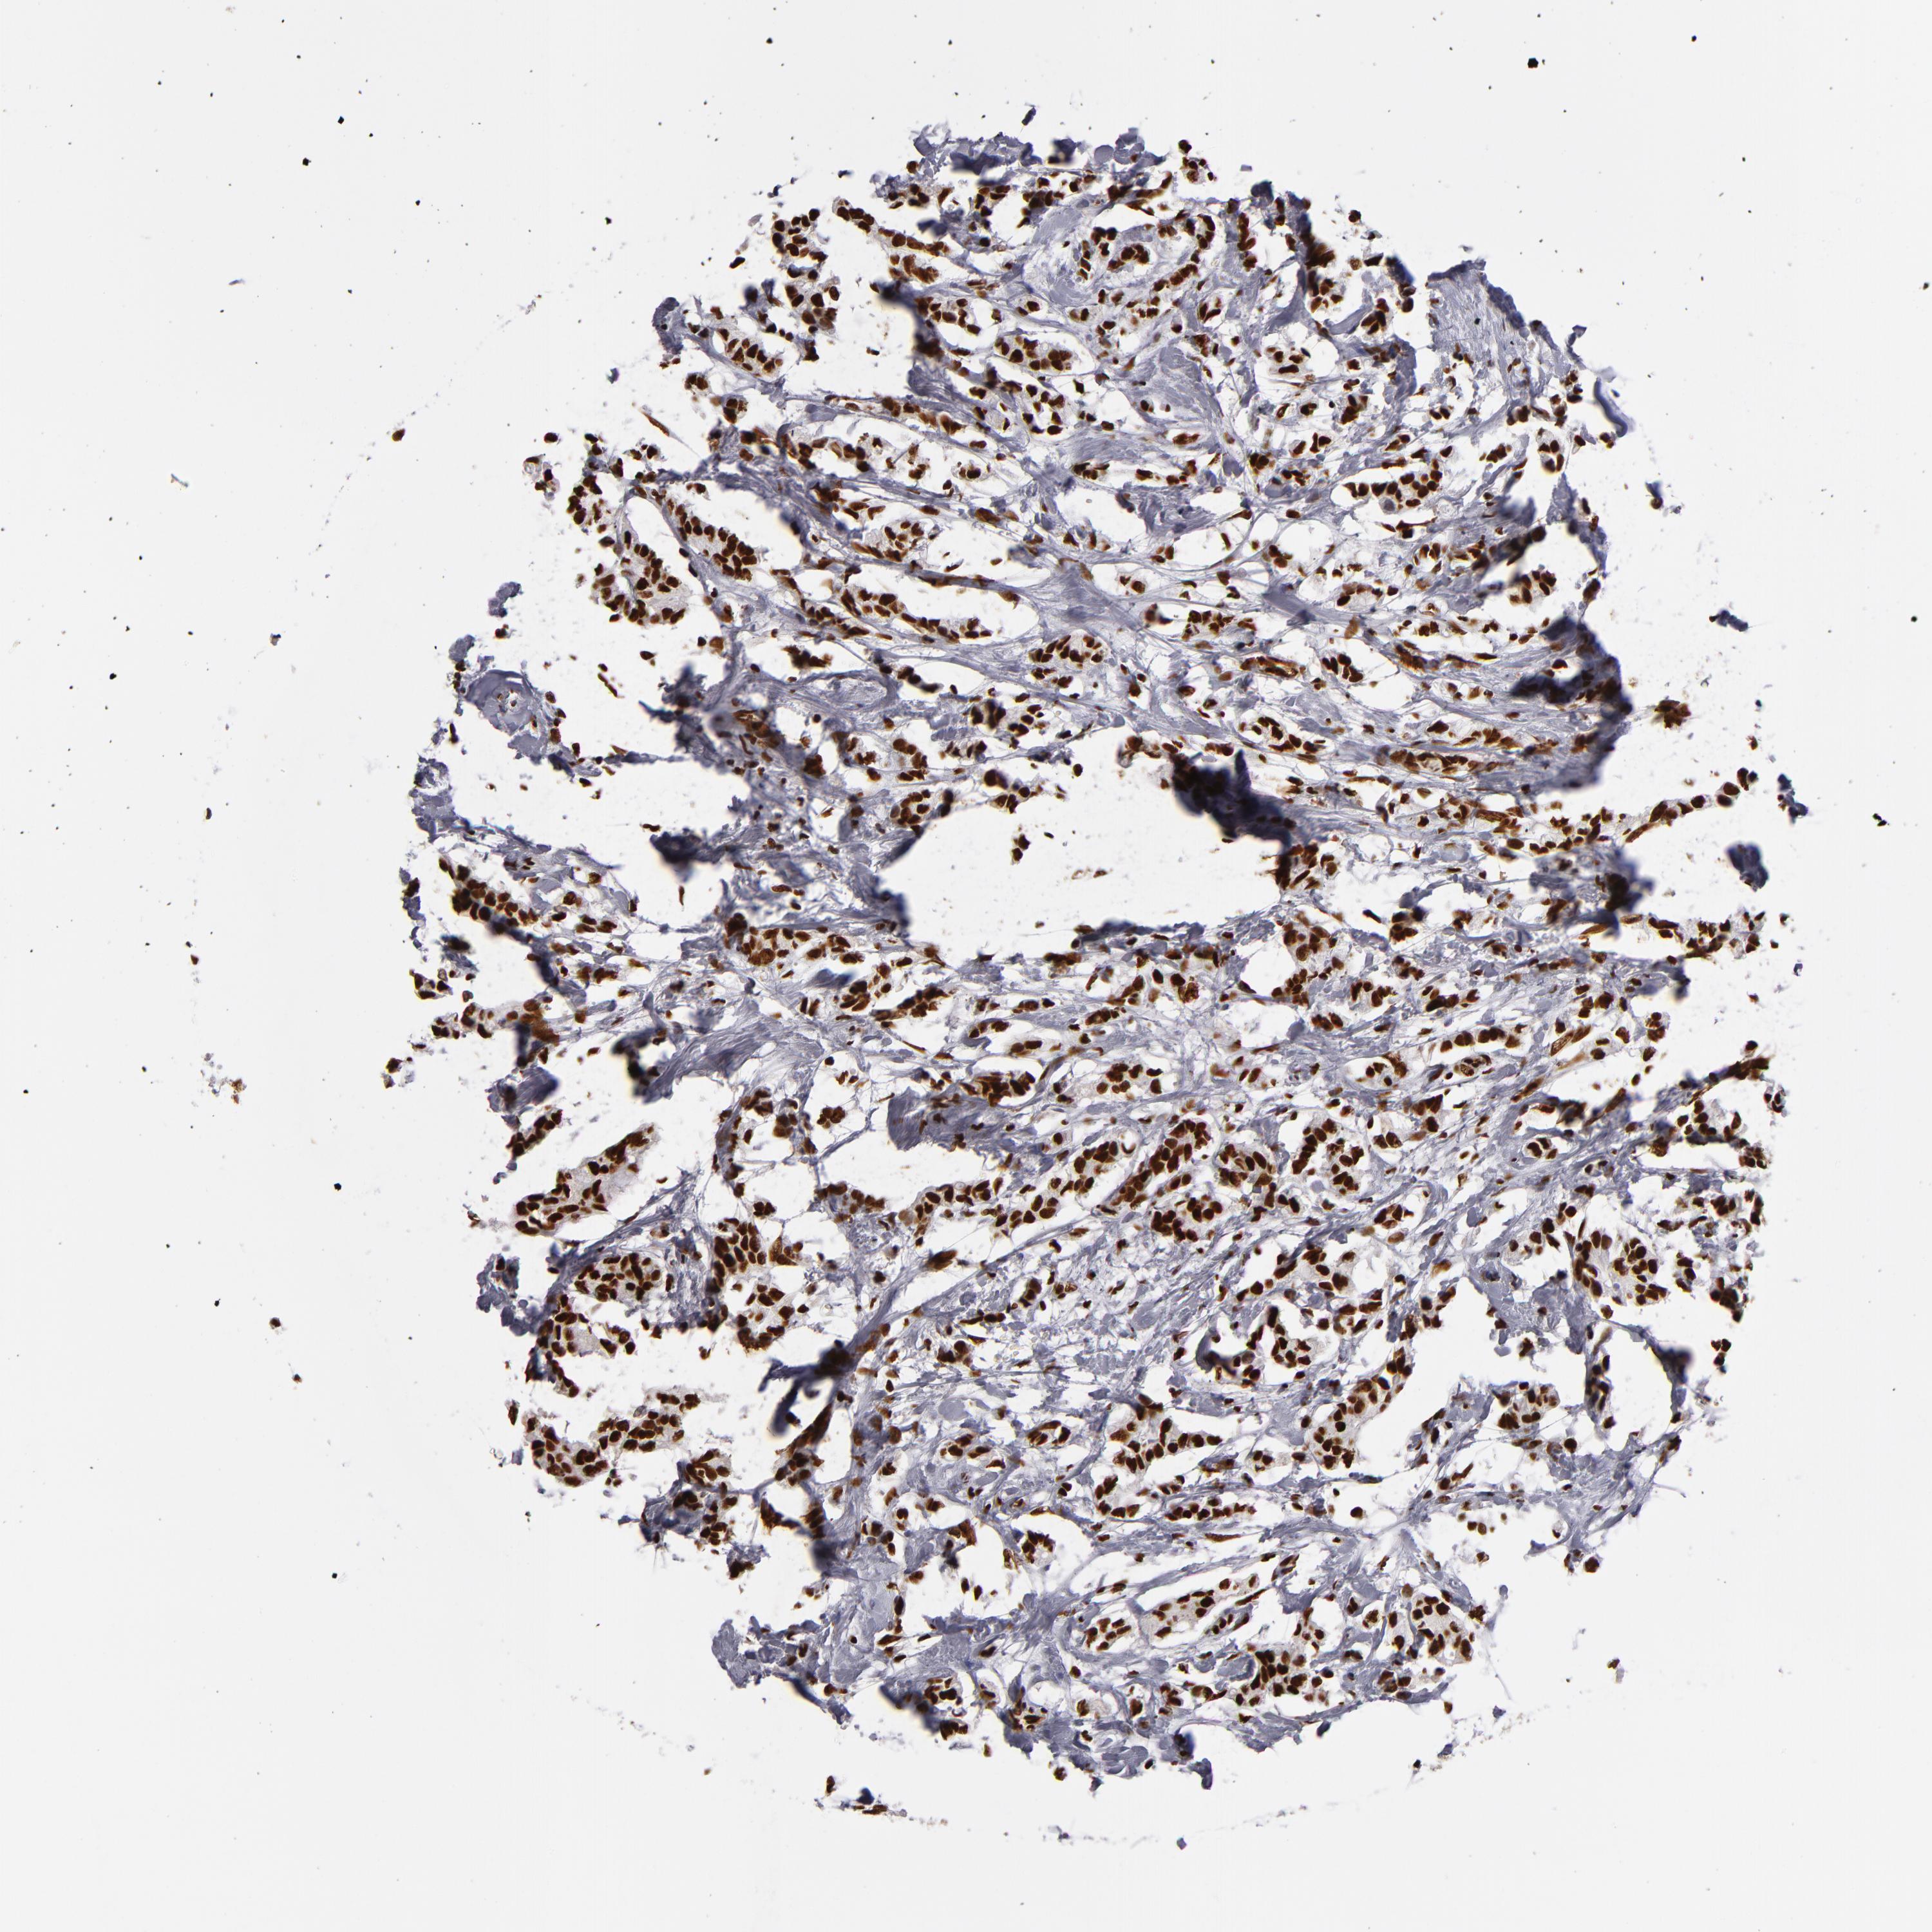

CANCER BREAST CANCER Show tissue menu

BRCA TCGA BRCA VALIDATION PROTEIN EXPRESSION